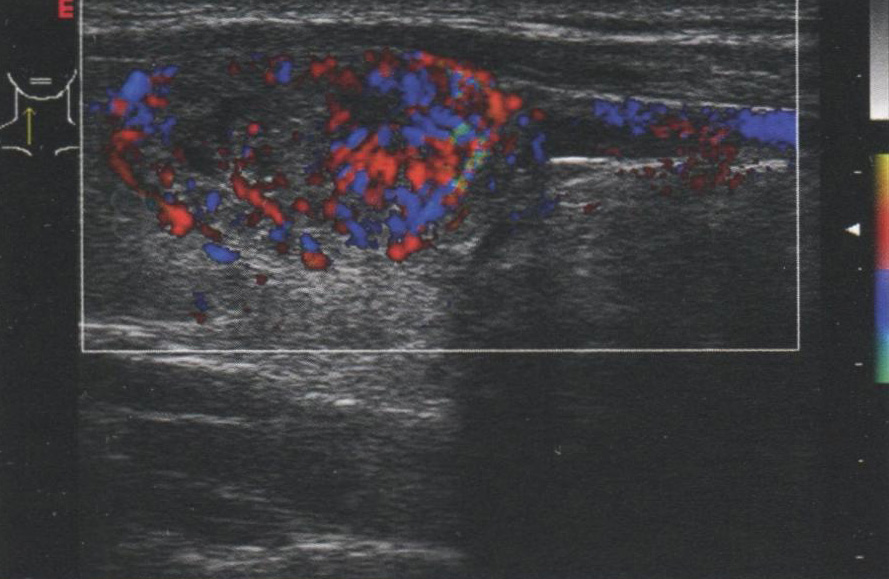

Рис. 3.4 демонстрирует фолликулярный рак в нижнем полюсе щитовидной железы (ЩЖ) с очень высоким уровнем кровотока. Визуализируется нижняя щитовидная артерия, кровоснабжающая узел. На рис. 3.5 показан узел, без значимой внутриузловой васкуляризации, лишь с немногочисленными сосудами на периферии. Этот узел — доброкачественная фолликулярная аденома.

Рис. 3.4. Васкуляризованный узел. Фолликулярный рак в нижнем полюсе щитовидной железы с выраженным кровотоком. Кровоснабжение узла происходит за счет нижней щитовидной артерии